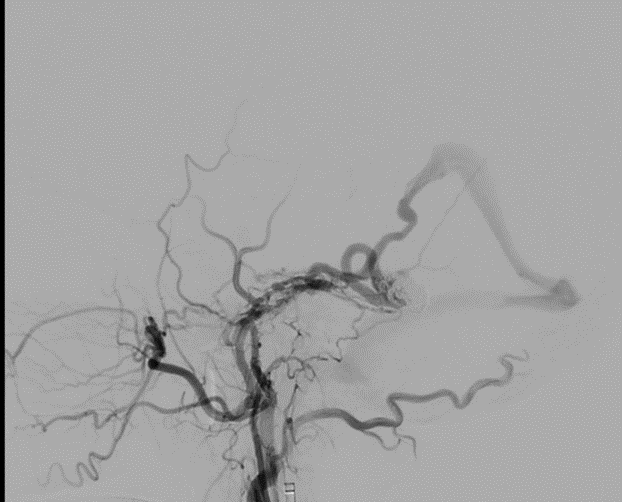

តាមរយៈស្នាមវះតូចមួយនៅភ្លៅ លោកវេជ្ជបណ្ឌិត Danh បានធ្វើអន្តរាគមន៍ដោយប្រុងប្រយ័ត្ននូវបំពង់ និងខ្សែមីក្រូ-មគ្គុទ្ទេសក៍តាមរយៈសរសៃវ៉ែន ដើម្បីឈានទៅដល់កន្លែងដាច់សរសៃឈាមក្នុងខួរក្បាល។ សរុបចំនួន 12 ខ្សែ (លួសដែក) ត្រូវបានដាក់នៅខាងក្នុងរន្ធសរសៃឈាមដើម្បី “បំណះ” តំបន់ដែលខូចនិងរារាំងលំហូរឈាមតាមរយៈការធ្លាយ។

ប៉ុន្មានម៉ោងក្រោយមកការធ្វើ អ្នកជំងឺមានស្ថេរភាព ដោយមិនមានការចង្អោរ និងកាត់បន្ថយការឈឺក្បាល។ ការស្កែន MRI ក្នុងរយៈពេលប៉ុន្មានថ្ងៃបន្ទាប់ បានបញ្ជាក់ថា ការហូរឈាមក្នុងខួរក្បាលលែងមាន និងកំពុងដោះស្រាយជាបណ្តើរៗ។ លោក F. ត្រូវបានចេញពីរមន្ទីរពេទ្យបន្ទាប់ពីការត្រួតពិនិត្យរយៈពេលពីរសប្តាហ៍។

ការព្យាបាល fistulas arteriovenous dural ឬ aneurysms ខួរក្បាលជាមួយនឹងការអន្តរាគមន៍ endovascular ផ្តល់នូវអត្ថប្រយោជន៍ច្រើនហើយមិនរងនូវផលប៉ះពាល់ខណៈពេលដែលសម្រេចបាននូវអត្រាជោគជ័យខ្ពស់។ ទោះជាយ៉ាងណាក៏ដោយ បច្ចេកទេសនេះត្រូវតែអនុវត្តនៅក្នុង Cathlab ទំនើប ហើយត្រូវការវេជ្ជបណ្ឌិតឯកទេសទាំងផ្នែក endovascular និង neurointerventional ។ មន្ទីរពេទ្យ FV ត្រូវបានបំពាក់ដោយ Cathlab ទំនើប និងប្រព័ន្ធរូបភាព DSA ដែលផ្តល់នូវរូបភាពសរសៃឈាមដែលមានគុណភាពបង្ហាញខ្ពស់ ដើម្បីបង្កើននីតិវិធីច្បាស់លាស់ និងកាត់បន្ថយពេលវេលាអន្តរាគមន៍។ វេជ្ជបណ្ឌិត Huynh Huu Danh អ្នកឯកទេសកម្រិត I គឺជាអ្នកឯកទេសខាងសរសៃឈាមដែលមានបទពិសោធន៍ម្នាក់ ដែលមានសមត្ថភាពអាចអនុវត្តនីតិវិធីទាំងនេះបានទាំងមនុស្សពេញវ័យ និងកុមារ។